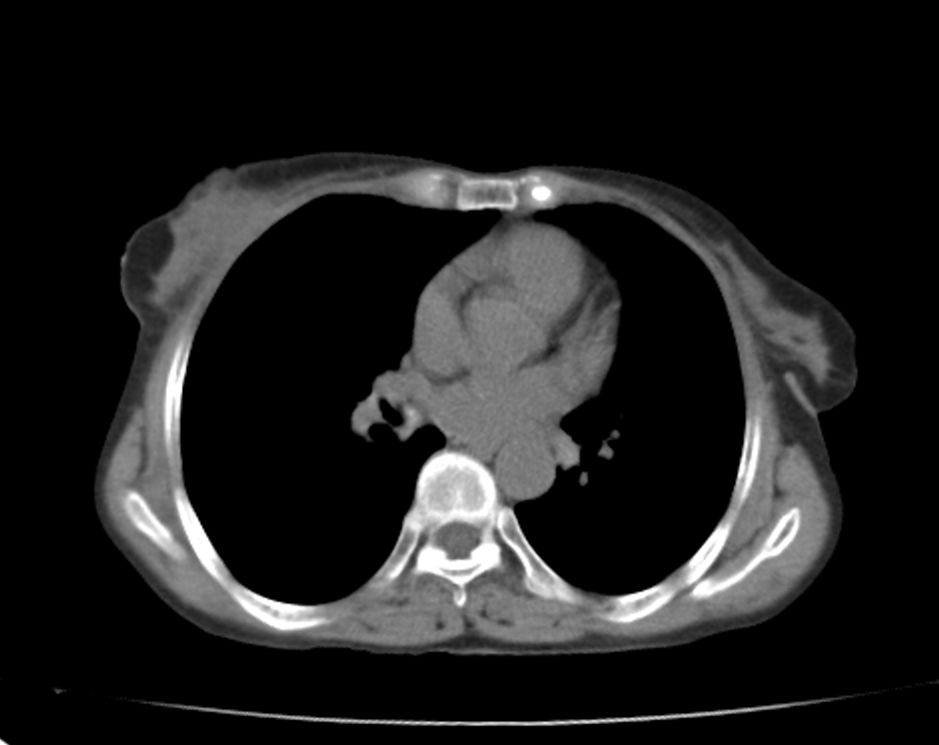

标题: CT21609:右乳包块1年,请各位讨论分析一下,乳腺CA, [打印本页]

标题: CT21609:右乳包块1年,请各位讨论分析一下,乳腺CA,

考虑---右乳癌并胸壁、肋骨、双肺转移。

考虑乳腺癌侵犯肋骨、胸壁及两肺转移可能性大。

右乳癌并胸壁、肋骨、双肺转移。

考虑右侧乳腺癌侵犯肋骨、胸壁及两肺转移。

支持考虑---右乳癌并胸壁、肋骨、双肺转移。

考虑右侧乳腺癌侵犯肋骨、胸壁及两肺转移可能。

考虑右侧乳癌并胸壁、肋骨及双肺多发性转移。